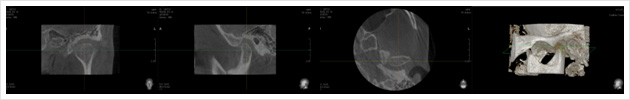

Panorama X-ray를 촬영하여 턱관절의 형태를 평가하기도 합니다. Panorama X-ray는 전반적인 치아의 형태나 치근, 아래턱뼈의 상태, 턱관절의 윤곽은 알 수 있지만 상의 왜곡으로 인해 정확한 턱관절의 형태를 평가하기는 어렵습니다.

턱관절의 형태 변화가 의심될 때에는 턱관절 3D CT를 촬영하여 평가하여야 합니다.

턱관절 3D CT를 통해 턱관절 내에서 아래턱 형태나 대략적인 위치를 평가할 수 있습니다. 그리고 턱관절 치료를 진행하면서 턱관절의 형태가 양호하게 회복되는지도 평가할 수 있습니다.

그 밖에도 턱관절 내에서 디스크가 어느 위치에 있는지 알아보기 위해서는 MRI 촬영검사가 필요합니다.

또한 턱관절 내의 골 흡수 진행 상태를 확인하기 위해 bone scan을 촬영하기도 합니다.